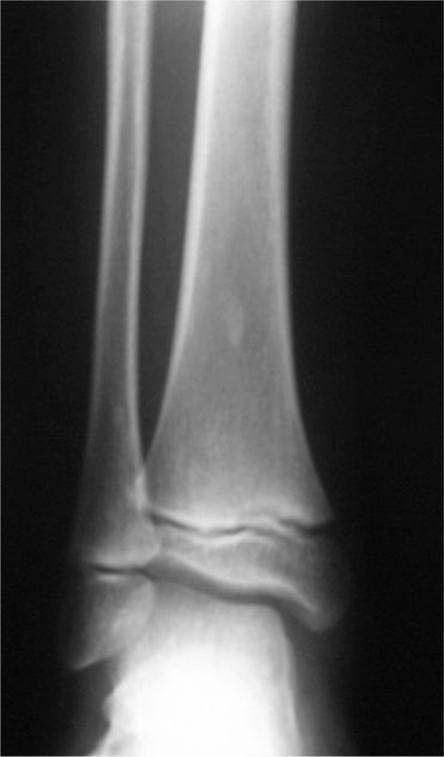

Osteopoikilosis is a rare asymptomatic sclerosing bony dysplasia of benign origin. It is usually found incidentally on radiological examinations. Familial occurrence indicates a genetic milieu with autosomal dominant pattern. Here, we present a case report of a young woman suffering from pelvic pain due to osteopoikilosis (OPK). The same disorder was later found in her son and daughter.

骨斑点症是一种罕见的良性起源的无症状硬化性骨发育异常。通常在影像学检查中偶然发现。家族性发病提示存在常染色体显性遗传模式的遗传背景。在此,我们报告一例因骨斑点症(OPK)导致骨盆疼痛的年轻女性病例。后来在她的儿子和女儿身上也发现了同样的病症。